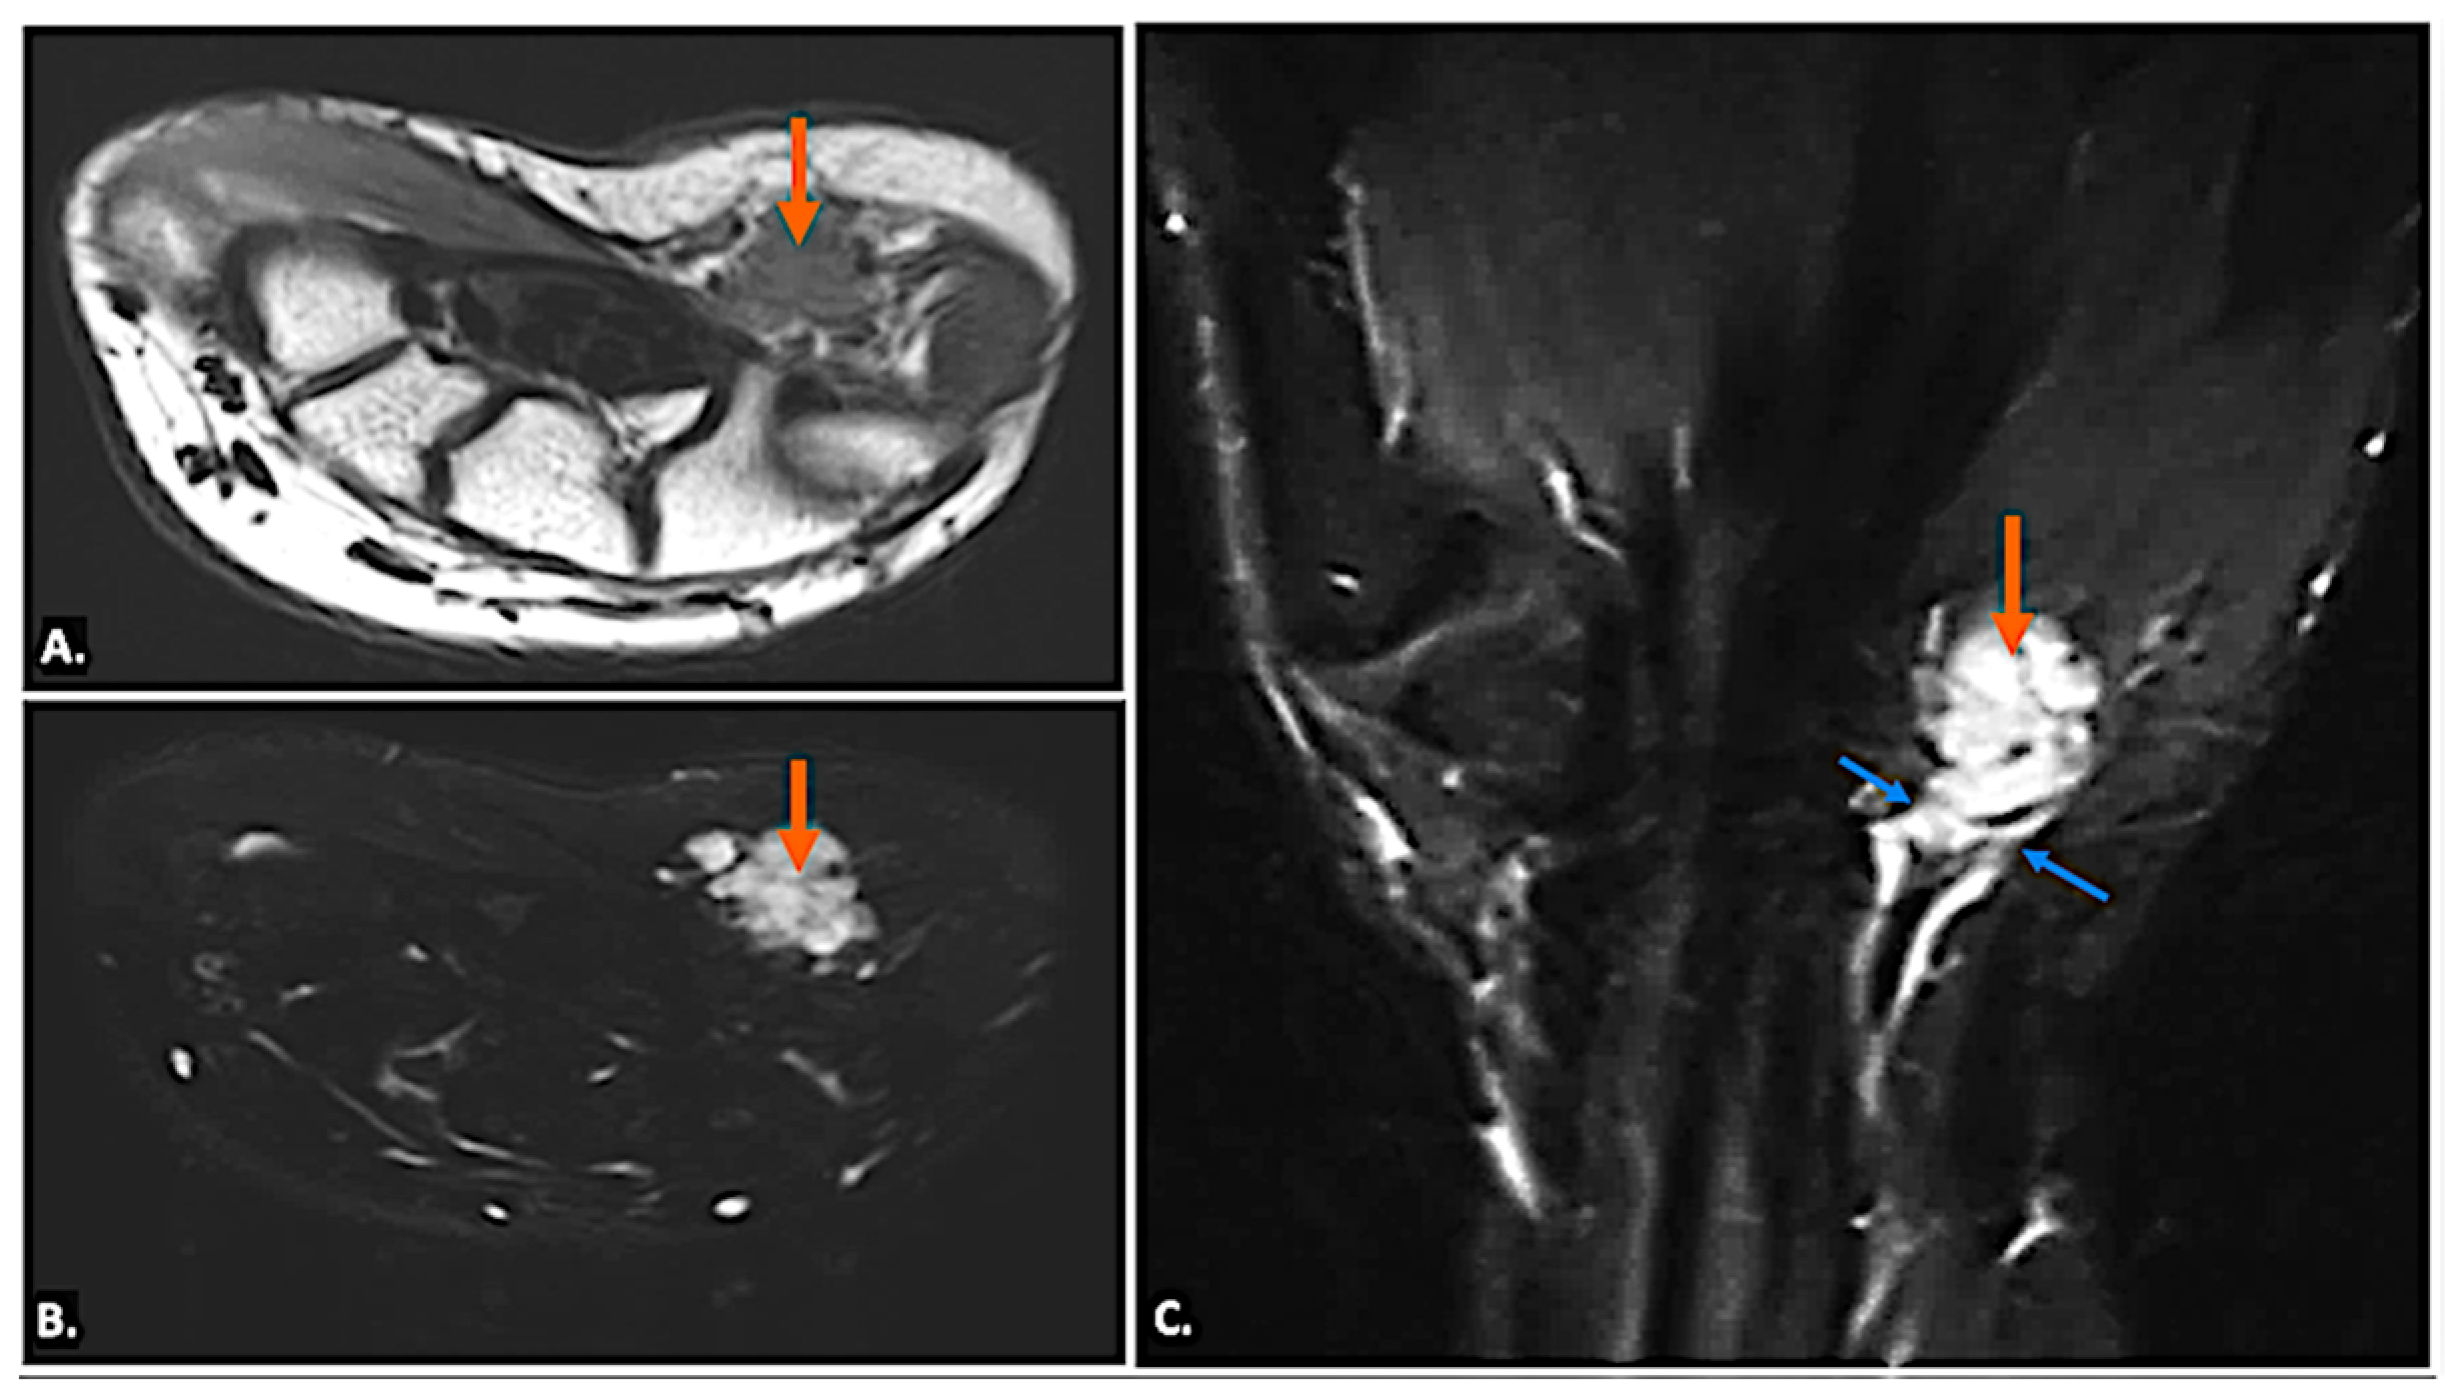

| Vascular Abnormalities (Aneurysms, Thrombosis, AVM) | Hypoechoic/anechoic mass with vascular flow (aneurysms) or absent flow (thrombosis) on Doppler. | Thrombosis: Low or high signal in vessel lumen on T1/T2 (depending on stage). Aneurysms: Well-circumscribed lesion with potential signal voids from high flow. |

| Traumatic Injuries (Hook of Hamate Fracture, HHS, Nerve Laceration, Stump Neuroma) | Nerve laceration: Hypoechoic discontinuity with possible neuroma formation (bulbous enlargement). Fractures: May be occult on standard radiograph and on ultrasound. HHS: Vascular abnormalities on Doppler. | Fractures: Best seen on CT/MRI if radiographs are inconclusive. Neuroma: T2 hyperintensity with possible nerve thickening and discontinuity. HHS: Aneurysm/thrombosis findings. |